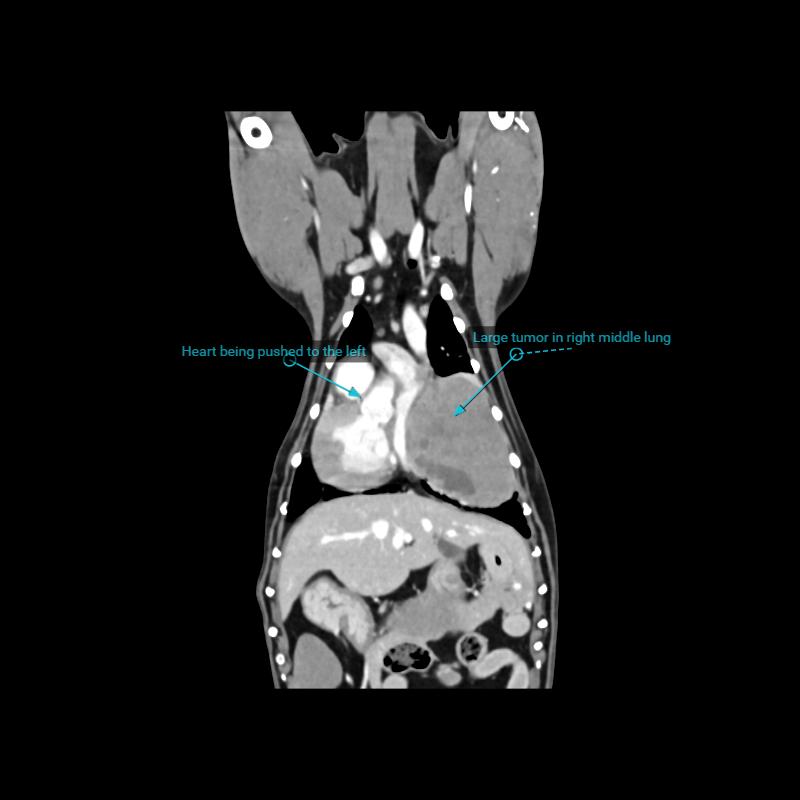

Spike’s CT went well and he’s back home sleeping off the anaesthetic. Here’s a summation of his clinical notes:

“ We performed a CT scan today to further evaluate Spike's lung mass. We confirmed the presence of a very large mass (about 6.5cm) in the right side of his chest. A final radiologist's report is pending to give us more detail about resectability, but initial review suggests that the surgeons would be able to remove the tumour as it currently is. Because it is so large, they would have to cut one of his ribs to make room to get it out. This tumour is large enough and compressive enough that the sooner the better in terms of surgical outcome. Right now he is compensating very well but it is right on the edge of compressing the heart significantly and would be more and more at risk of invading the airways and affecting how much the surgeons could remove.”

Spike’s insurance policy renews in early November, however after today’s CT scan, I have reached the limit of his entitlement for this year. Since Spike needs surgery ASAP, I will not be able to claim insurance for the removal of his tumour as the vet has stressed a delay in treatment could seriously impact the outcome of its removal. He is tentatively booked in for surgery next Wednesday the 9th October if I can raise the funds.

The image below shows the size of Spike’s tumour. I’ve also shared an image of healthy lungs and heart (the lungs are the black areas in the chest cavity) for comparison.